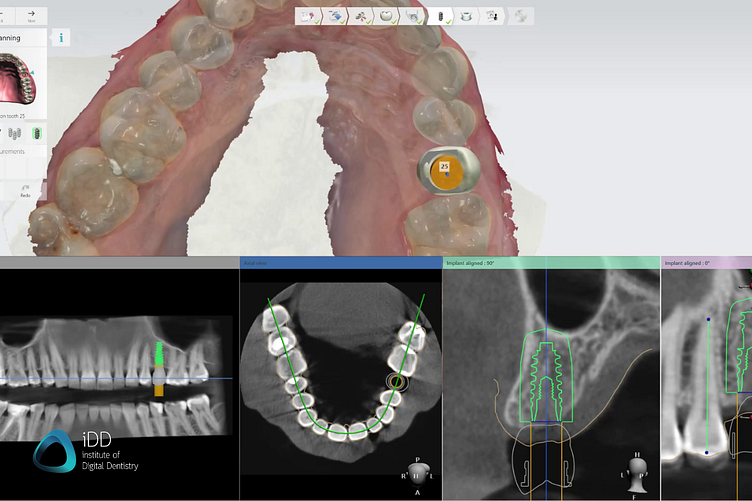

Specialized software is used to plan the implant surgery ad design the surgical guide based on the digital models obtained.

In this case, we used Implant Studio by 3Shape, but there are many implant planning software available, some of them even for free with a pay-per-export option. 3Shape is just our favorite by far due to its ease of use and slick workflow.

Most software follows a so-called restoratively-driven implant planning workflow. This means, that a digital model of the future crown/restoration is used to help you plan out the ideal implant position. This way, you can prevent placing an implant with a screw channel opening coming through the buccal aspect or cusps.

Using the implant planning software, several factors such as adjacent teeth and bone density can also be addressed and accounted for. Additionally, you will be prompted to mark the inferior alveolar nerve when planning for a mandibular implant, and it makes it easy to account for sinuses as well as maxillary implants.

Within the same software, you get to choose your preferred implant brand, as well as the fixture type, width, and length for the implant company of your choice. This is done by importing the digital library of the brand of implant you want - something that can be obtained from the sales rep/company website. Implant planning software is generally open, meaning that you can download the digital libraries for any implant company.

For a restorative-driven workflow, a digital tooth mock-up is used to help find the most aesthetic and functional implant position. CBCT data help you account for bone density, sinus, or inferior alveolar nerve.

When designing the surgical guide itself - this is actually quite a straightforward task and shouldn’t take more than a couple of minutes.

You get to also design the size of your guide. For a single-unit case, it’s generally recommended to extend the guide over at least an entire quadrant, as you will achieve more stability from fitting the guide to more teeth. You can add cutouts to help you verify proper seating in the patient’s mouth or add the patient’s ID.

The design and digital library of the implant guide also accounts for a metal sleeve if required for your guide, that is purchased from the distributor and later inserted into your guide.

The surgical guide can be either created as a pilot guide - for use with the initial pilot drill only or fully guided - to assist you throughout the entire drill sequence. This depends on the surgical kit of your choice.

The surgical guide design is very straightforward and fully customizable. In the step pictured above, the dental technician (Hugh Cho) is adding windows to help assess proper seating in the patient’s mouth.